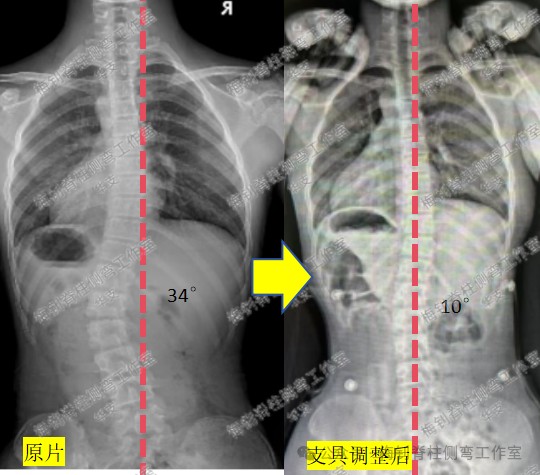

14岁女孩,生长末期,复查拍片后,被骨科医生告知,侧弯加重了,支具不合格,建议更换。家长马上比较忧虑,孩子也急哭了。家长马上把片子发给我们,当看到片子我们放心了:复查片力线明显好转,腰椎下半段明显变直,顶椎偏移程度降低,侧弯度数好转不多,但没有加重,只是医生测量的“加重”,所以,X线片复查结果整体向好。后面孩子来复查,体表的好转也印证了侧弯整体向好的结果。

为了彻底消除家长的顾虑,支具根据现状稍作调整后,再次拍片查看,结果比较理想,家长也彻底放心了。对于该骨科医生的建议,我们不做评论,或许他真的不懂吧~

生长末期,矫正不易,希望孩子重拾信心,最终有好的结果。